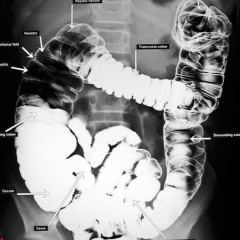

На нормальной рентгенограмме толстой кишки с двойным контрастированием форма и размеры органа остаются неизменными, не наблюдаются сужения или расширения просвета, а контрастное вещество равномерно распределено по стенкам. Складчатость слизистой оболочки соответствует норме.

После подготовки выполняется обзорная рентгенография органов брюшной полости. Затем в кишечник с помощью клизмы вводится контрастное вещество, и, меняя положение пациента (на боку, на животе, на спине, стоя), делают несколько дополнительных снимков. Последний снимок делается после опорожнения кишечника. При двойном контрастировании на заключительном этапе кишечник наполняется воздухом для получения изображений его внутренней поверхности.

После подготовки проводится обзорная рентгенография органов брюшной полости. Затем в кишечник вводится контрастное вещество с помощью клизмы, и выполняются дополнительные снимки в разных положениях пациента (на боку, на животе, на спине, стоя). Последний снимок делают после опорожнения кишечника. При двойном контрастировании на заключительном этапе кишечник наполняется воздухом для получения изображений рельефной внутренней поверхности.

Что можно увидеть на рентгеновских снимках кишечника с контрастом?

изменение просвета кишечника (сужение или расширение) и увеличение длины органа (удлинение толстого кишечника; значительное расширение просвета в области сигмовидной кишки);

изменение формы и положения кишечника;

наличие дефектов наполнения (мелкие опухоли в кишечнике; злокачественная опухоль, приводящая к сужению просвета восходящей ободочной кишки);

дефекты заполнения (указывает на выпячивания и углубления в стенках органа, куда проникает контрастное вещество; множественные дивертикулы);

наличие нескольких уровней жидкости в кишечнике, «чаши Клойбера» (скопления темного воздуха над жидкостью с горизонтальным уровнем светлого цвета — признак кишечной непроходимости).